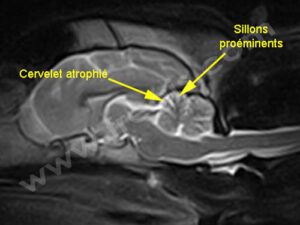

Chien avec une ataxie cérébelleuse héréditaire. L’IRM montre un cervelet atrophié avec proéminence des sillons (sulci)